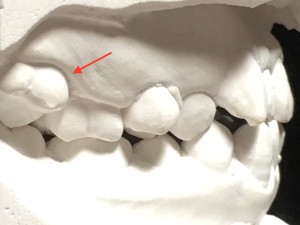

鋏✂️状咬合ってご存知ですか?

鋏状咬合(シザーズバイト)とは、上下の歯を噛み合わせた時に、上の歯の内側に下の歯が軽く接触し、鋏(ハサミ)のような状態になるかみ合わせのことです。

このようなかみ合わせになると、咀嚼機能が不十分で、顎運動が制限されます。

鋏のように、すれ違うようにあたるので、咬合支持がないので、歯牙や顎関節への過剰な負担が生じる可能性があります。

下顎は、上顎の中で自由に動けないといけません。女の子は、左右第二大臼歯共に、鋏状咬合でした。左右共に、運動が阻害されてしまいます。